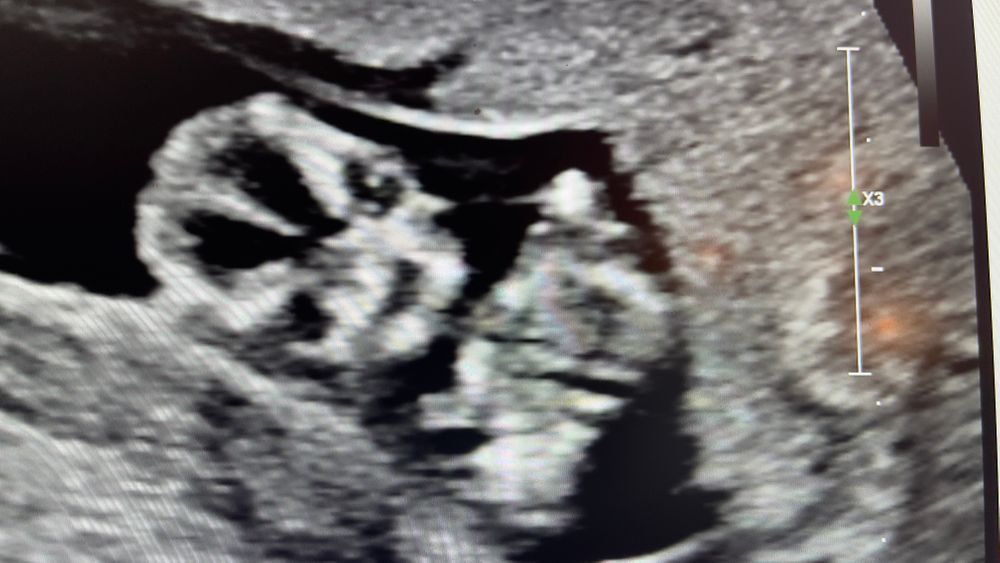

Температура 37.7-38,2 в 14 недель

Товарищи что сделать и опасно ли это состояние ? По мимо дикого токсикоза ещё и ломка костей с температурой добавилось 🤦🏻‍♀️Мне кажется я в пути на тот свет 😭

п.с. Была в госпитале сделали тест на Ковид, ещё не известен результат. Сказали возможно простуда, взяли все анализы , узи , все в норме . Отправили домой пить толенол не больше 4